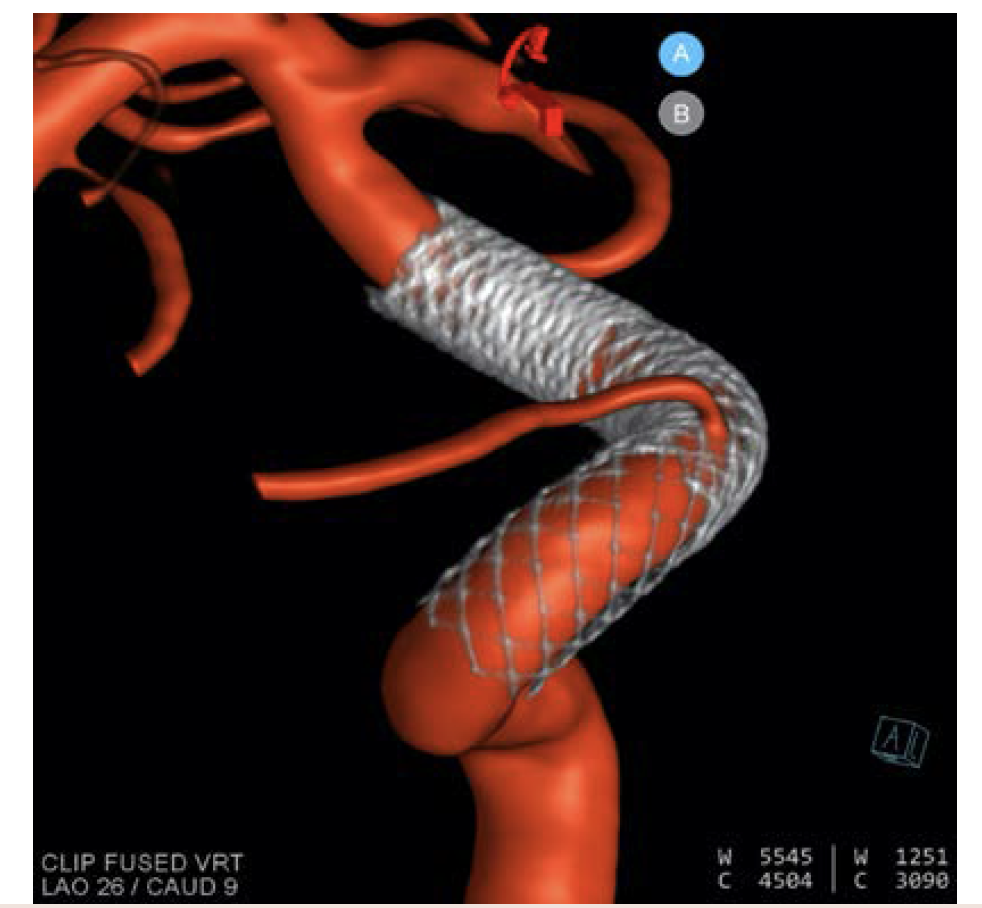

arteriograms of the entire head. I then finish with a syngo DynaCT Micro (Siemens Healthcare AG) with contrast, which provides extraordinary resolution of the stent construct, including stent-stent apposition, stent-wall apposition, and any central filling defects (Figure 5).

How do you verify flow diverter apposition?

As we use more braided devices, either of the intrasaccular or endoluminal variety, the verification of coverage across an aneurysm neck, device-device apposition, and device-wall apposition becomes increasingly important. The resolution afforded by DynaCT Micro is without parallel and not only gives us a unique opportunity to modify constructs with the patient still on the table, but also changes the way we approach device construction and the way we understand efficacy. There are no planar images that afford even close to the resolution of DynaCT Micro.

A 3D reconstruction of the aneurysm and DynaCT Micro image of the stent construct was performed (Figure 8). This is a 3-stent construct. There was extraordinary coverage over the neck of the aneurysm with 2-stent coverage over the distal ophthalmic segment and 1-stent coverage extending into the cavernous segment.

After a 3-stent construct was built, a DynaCT Micro with contrast was obtained, which demonstrated excellent stent-stent and stent-wall apposition (Figure 15). Even more important, it resolved an entire collateral arcade, replacing the native basilar artery and extending from the distal left vertebral artery (no stent covering the origin) to the distal basilar artery (1-stent coverage). This anatomic resolution enabled a more aggressive approach to the aneurysm neck, and ultimately 6 stents were placed. This anatomic collateral has previously been theorized and assumed to occur in the setting of giant midbasilar aneurysms without infarct. However, with DynaCT Micro, it can actually be visualized.